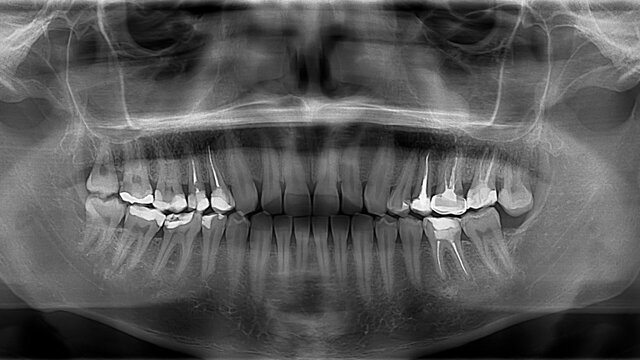

• Rayos X

Rayos X

El primer aparato de rayos X para la boca, lo que se conoce como placa periapical o dental, evolucionando luego a la ortopantomografía (radiografía general de la boca) y la resonancia magnética, que ya no utiliza los rayos X.